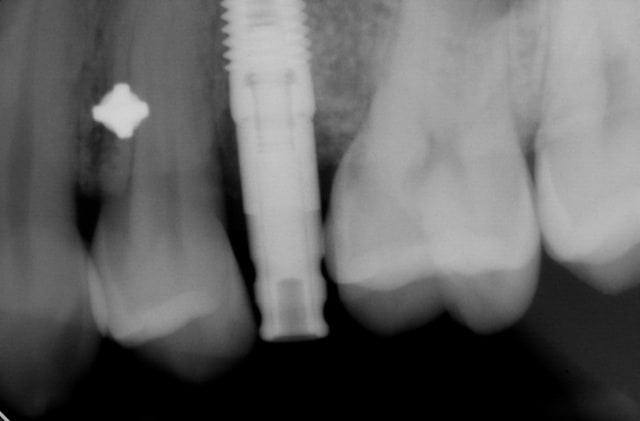

Bonsoir j'ai envoyé il y a plus d'un an chez mon implanto ce patient pour poser un implant pour remplacer la 25.

C'est avant qu'il fallait mesurer malheureusement il est un peu tard l'espace était trop réduit à la base (il me semble que ton implant est de 3.5 de diam) il te fallait un espace mésio distal plus important (6.5 mini).

L'odf ici relativement pratique car on a un ancrage absolue avec l'implant (ce qui n'est pas le cas avec une minivisse).

Un ressort en niti pour distaler la 6 ?